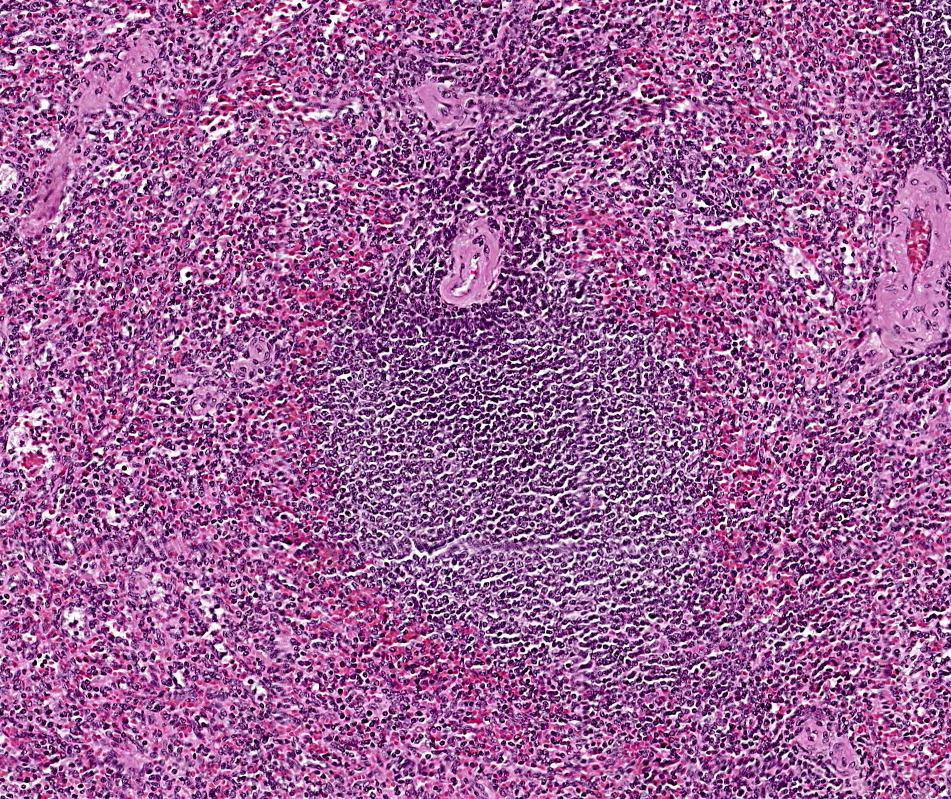

TIMO

Órgano linfoide 1° (primario)

Se compone de una cápsula de TC, una corteza basófila y una médula.

NO hay nódulos linfáticos.

En la médula es posible observar los Corpúsculos de Hassal formados por las células reticuloepiteliales de tipo VI.

El timo es un órgano encapsulado organizado en lóbulosEl timo es un órgano linfoide que carece de nódulos linfáticos y se encarga de la maduración de los linfocitos T.Observe la cápsula de tejido conjuntivo denso irregular que rodea este órgano linfoideEs posible observar gránulos de queratohialina en los corpúsculos de Hassall.La corteza tímica es altamente basófila y encontramos células reticulares epiteliales de tipo I, II, y IIILa médula del timo es fácil de identificar por la presencia de corpúsculos de HasallTimo, HyE.Los corpúsculos de Hassall secretan citocina hematopoyética para ayudar a la maduración de los LTEn la médula tímica es posible observar los Corpúsculos de Hassal formados por las células reticuloepiteliales de tipo VI.Observe la organización del timo, este carece de nódulos linfoides. Timo, HyE.Identifique los septos conjuntivos que organizan el lobulillos al timo.Identifique la basofilia de la corteza en comparación con la médula.En la adolescencia este órgano involuciona a tejido adiposo.Timo adulto, HyE.